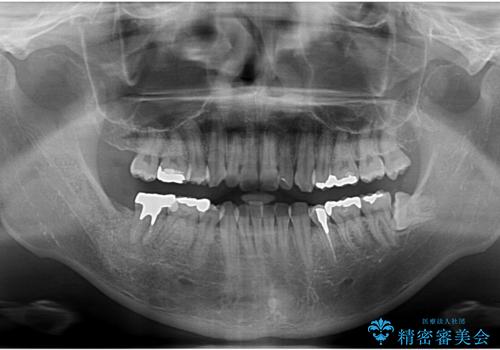

- 銀歯を白くしたいとのことで来院。

右下の被せ物を外し虫歯を除去したところ虫歯が深く保存が難しい状態だったので抜歯を行いました。

手前の銀の詰め物のところは除去して拡大鏡下で虫歯を取り除き、ジルコニアクラウンで治療を行いました。

抜歯したところは抜歯後骨の治癒を待ち、CTを撮影しインプラント治療ができる事(骨の厚みなど)確認し治療を行いました。